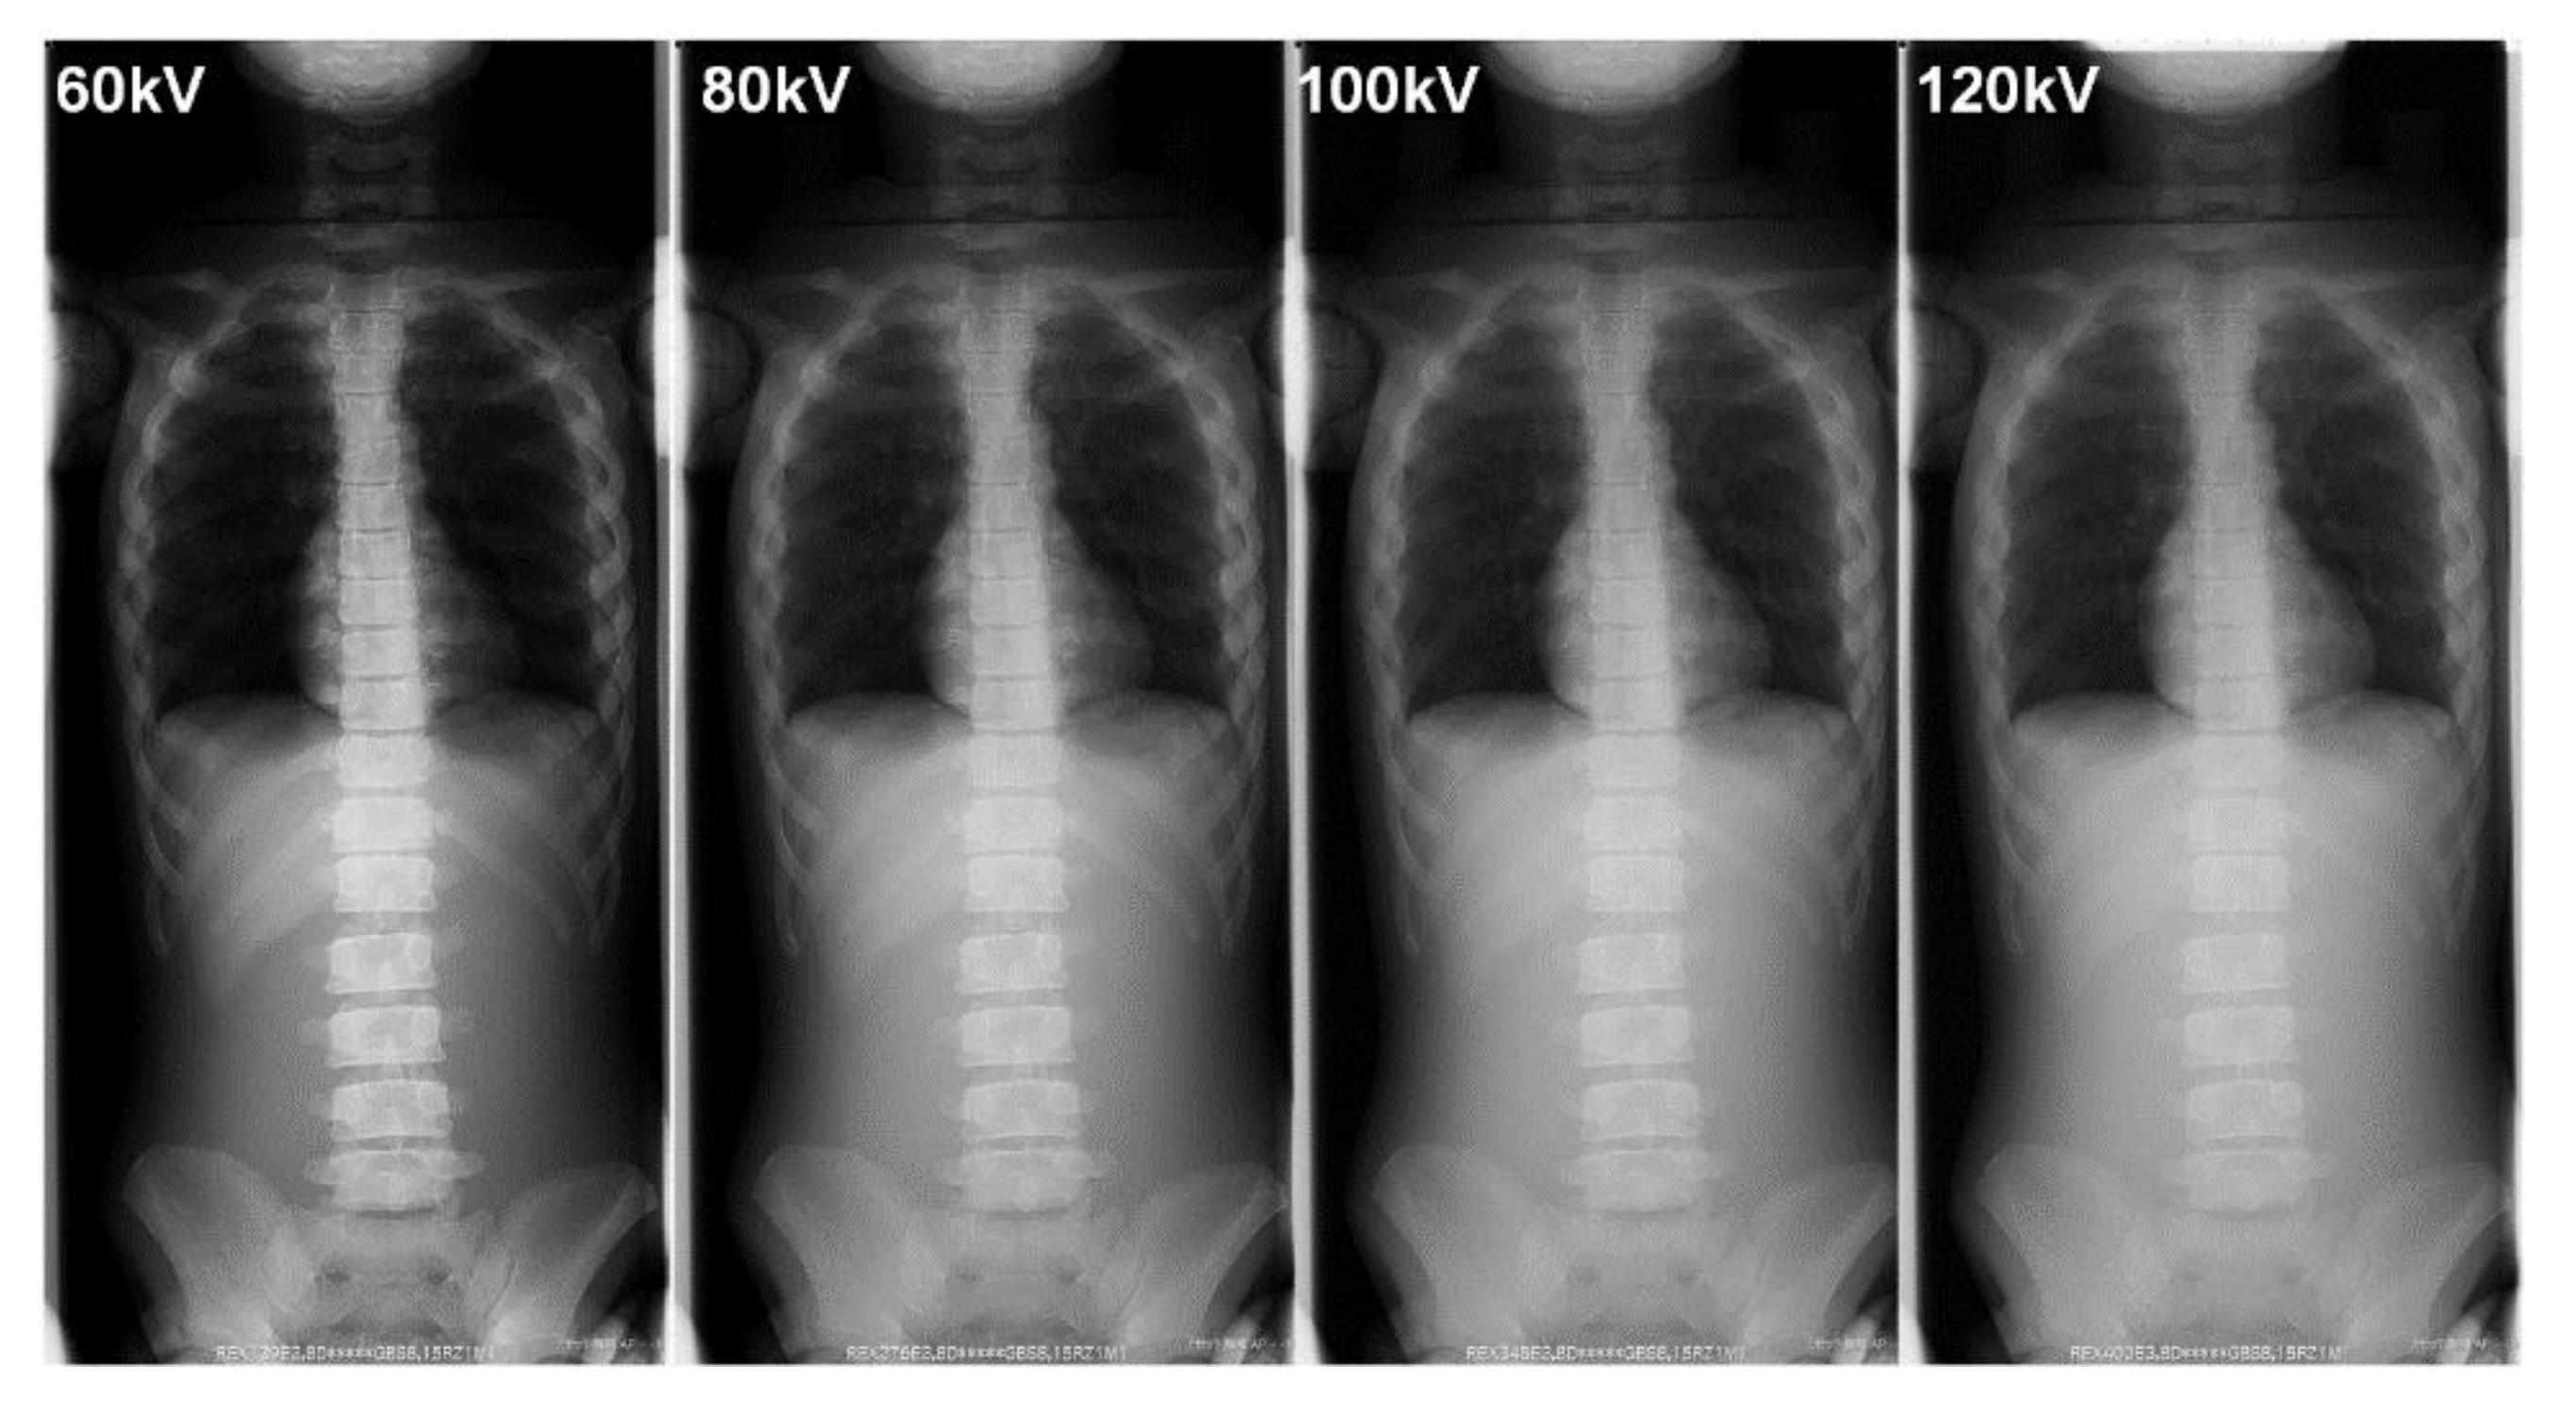

Table 5 summarizes the BSDs and the technical parameters during the FRs. Figure 8 and Figure 9 show examples of FRs taken in our phantom research.

Although the X-ray image contrast decreased with increasing tube voltage, the outline of the spine could still be recognized (Figure 8 and Figure 9). Even if the contour of the spine was not clear in the lower contrast image (lower dose, i.e., high voltage without a grid), the Cobb angle, which is a clinical indicator of the progress of scoliosis, could still be measured. In addition, image-processing technology, such as bone emphasis processing, is improving because of the use of digital photography. Hence, it may be possible to further reduce radiation doses during FRs and still obtain images that can be used to measure parameters, such as the Cobb angle, for clinical diagnoses, even under conditions that result in low image quality.

Figure 8. The differences in the phantom image contrast of full spinal radiographs using various tube voltages (focus-image-receptor distance: 180 cm, without a grid).

Figure 9. The differences in the phantom image contrast of full-spinal radiographs using various tube voltages (focus-image-receptor distance: 180 cm, with a grid).